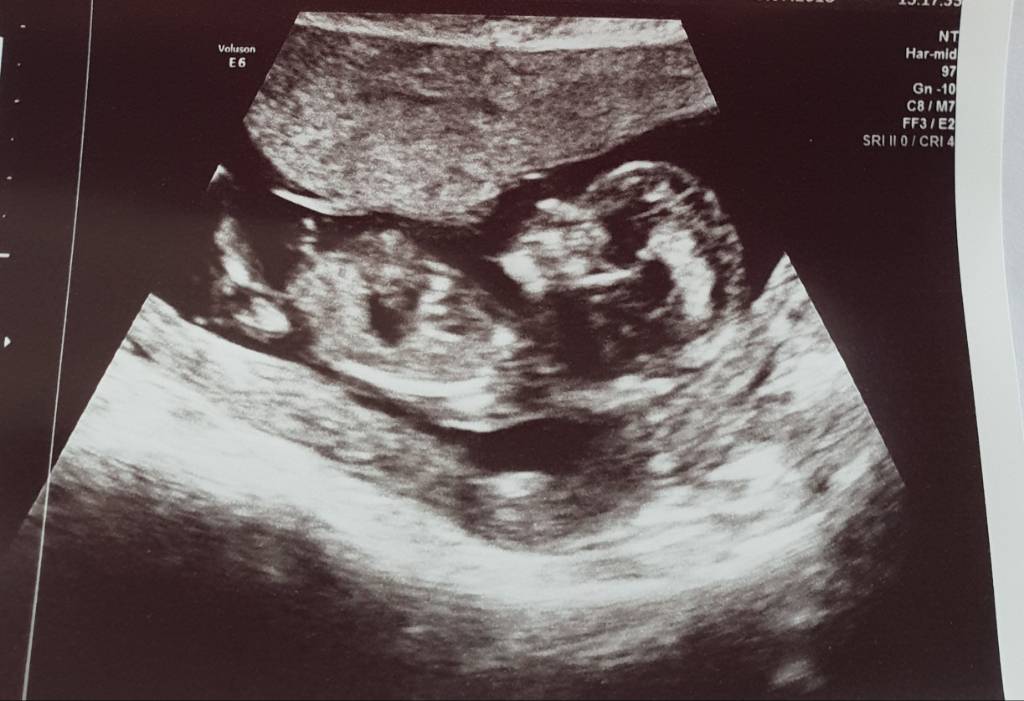

I have been suggested the dot under the nub means likely boy by one person but then others say the dot needs to be above for that? Any help appreciated :)

This little one looks like a girl to me :happy:

Leaning girl but the nub could still rise as it's early.

At this point in time it's really too early to guess with certainty because all babies start off looking like girls and once the testosterone kicks in, then and only then do "girl" parts turn into boy parts on some babies. For now, I agree that looks girly but don't get your hopes sky high yet because until the end of the 13th week, babies that look quite girly can still end up being boys. Deffo better than seeing a big ding dong at the 12 week scan though! :)